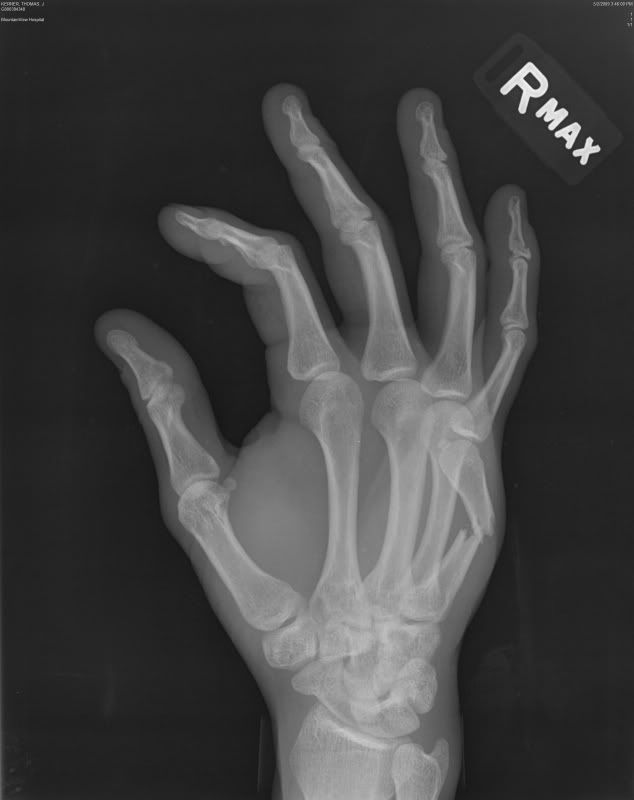

Pain in the Hand After Punching a Wall Journal of Urgent Care Medicine

From www.jucm.com

Pain in the Hand After Punching a Wall Journal of Urgent Care Medicine Hands Hurt After Punching Boxer’s fractures get their name for how they usually happen: Boxer’s fracture are very common hand injuries. If you are experiencing serious medical symptoms, please see the national library of medicine’s list of signs you need emergency medical attention or call 911. These injuries can also occur in contact sports, automobile collisions, altercations, or falling to the ground on an. Hands Hurt After Punching.